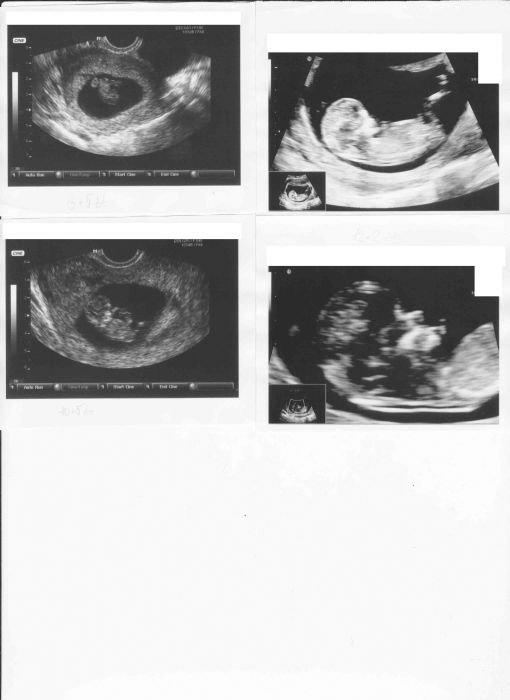

U tech čtyř obrázku- v levo nahoře 8+5tt, v levo dole 10+5 a v pravo nahoře a dole(obličej) 12+2